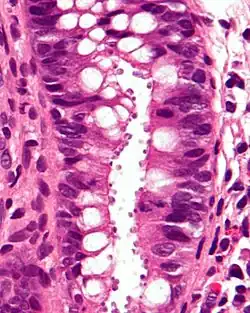

Micrograph showing cryptosporidiosis. The cryptosporidium are the small, round bodies in apical vacuoles on the surface of the epithelium. H&E stain. Colonic biopsy.

Other staining techniques include acid-fast staining,[28] which will stain the oocysts red.[27] One type of acid-fast stain is the Kinyoun stain.[23] Giemsa staining can also be performed.[24] Part of the small intestine can be stained with hematoxylin and eosin (H & E), which will show oocysts attached to the epithelial cells.[27]